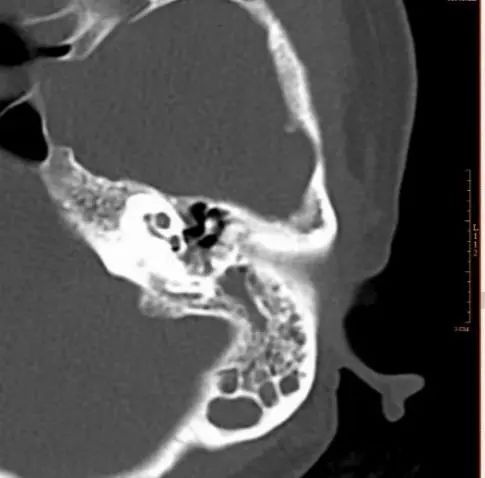

在耳内镜,听力学以及颞骨CT等相关检查后发现,安女士的鼓膜已经明显内陷,鼓室里的积液呈蓝棕色,听力检查提示传导性耳聋,颞骨CT也提示鼓室及乳突里积液。

颞骨CT检查。